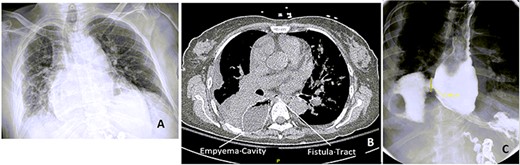

Esophagograms at various stages postadmission showing improvement in the size of the esophageal defect. (A and B) d13 and d19 Postadmission, respectively. NP tube in place ending into the right pleural space cavity. (C) d26 Postadmission with NP tube now retracted 5 cm, with decrease in the contrast extravasation seen. (D) d33 Postadmission with NP tube now removed showing no contrast extravasation seen with defect now healed. (E) CXR d41 postadmission showing improved right-sided pleural effusion and consolidation with no NP tube in place. (F) Outpatient follow-up esophagogram (d64 postadmission), (NP—nasopleural).

We found that by day 16 (d16) postdiagnosis of perforation, we were able to start pulling back on the tube. Further pulling back of the NP was dictated by improvement we saw on subsequent esophagograms. By d30, NP was removed and follow-up of esophagogram on d33 showed no extravasation of the contrast, suggesting healed perforation. She was started on sips of water and diet slowly advanced with soft regular diet 2 weeks postdischarge (Figs 2 and 3).